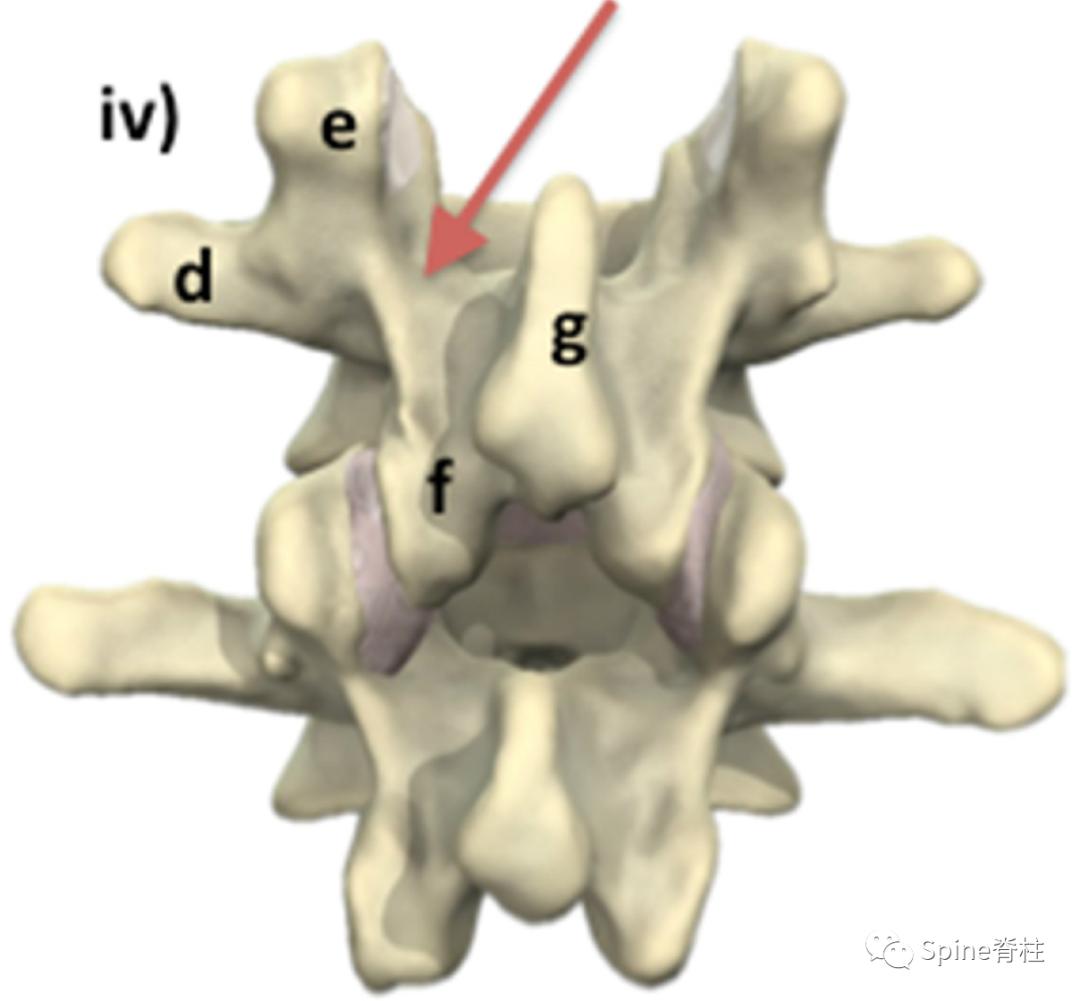

腰椎的解剖和峡部位置 。从侧位(i)向右逐渐旋转至正位(iv)观察。 红色箭头处为峡部 。a=椎体;b=椎间盘;c=椎弓根;d=横突;e=上关节突;f=下关节突;g=棘突;h=椎板。PMID: 30396669